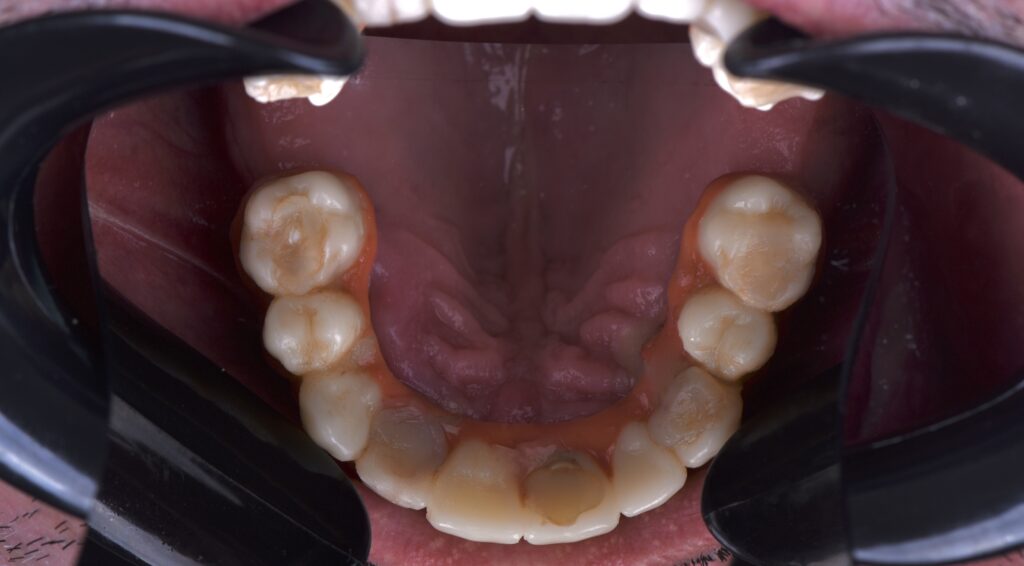

Fig. 1

During the clinical examination, the absence of various teeth and compromised carious crowns and roots on both the upper and lower arch, loss of vertical dimension, bone loss, and absence of occlusal plane were observed. This condition left the patient in social and emotional distress.